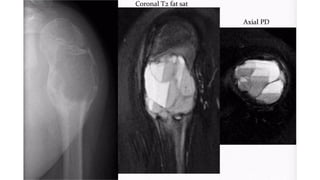

Benign tumor arising from fat -

Intraosseous Lipoma

• Extremely rare

• • Age

• • Wide range = 5-85 years

• • Usually detected in 4th-5th decades

• • L o c a t i o n

• • Lower limb = 75% ( metaphysis)

• • Calcaneum>femur >tibia>fibula

• • Upper limb

• • Skull and mandible

• • Spine & pelvis

• • Ribs

Plain radiograph feature

• Expansile radiolucent lesion with sharply defined

• sclerotic margin

• • No periosteal new bone formation

• Within calcaneum, lipoma has characteristic

• appearance, osteolytic lesion with a central focus

• o f o s s i fi c a t i o n

• CT & MRI

• • Can be homogenous fat content

• • Fatty lesion with central necroses, central

• calcifications o r o s s i fi c a t i o n s

• • Fatty lesion with multiple central necroses, central

• calcifications or ossifications

Differentials for intraosseous lipoma - SBC and Bone infarct